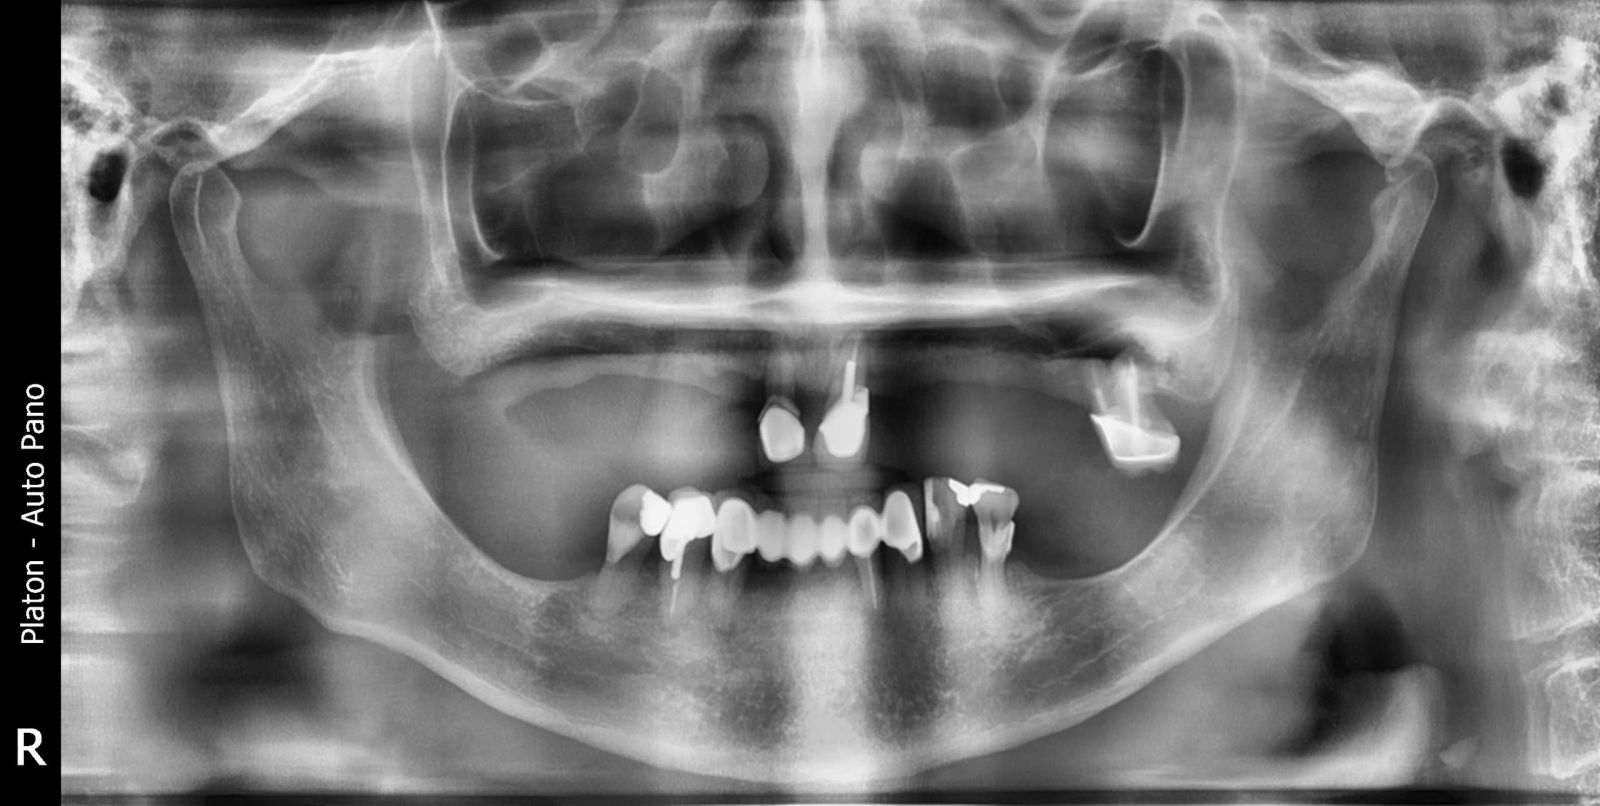

Trước điều trị, chú gặp tình trạng mất gần như toàn bộ răng, gây khó khăn khi ăn nhai và ảnh hưởng lớn đến thẩm mỹ khuôn mặt.

Sau khi được bác sĩ thăm khám, chụp phim 3D và lên kế hoạch điều trị cá nhân hóa, đội ngũ chuyên môn đã tiến hành đặt 6 trụ Implant chiến lược trên mỗi hàm, tạo nền vững chắc để phục hình cố định toàn bộ răng.